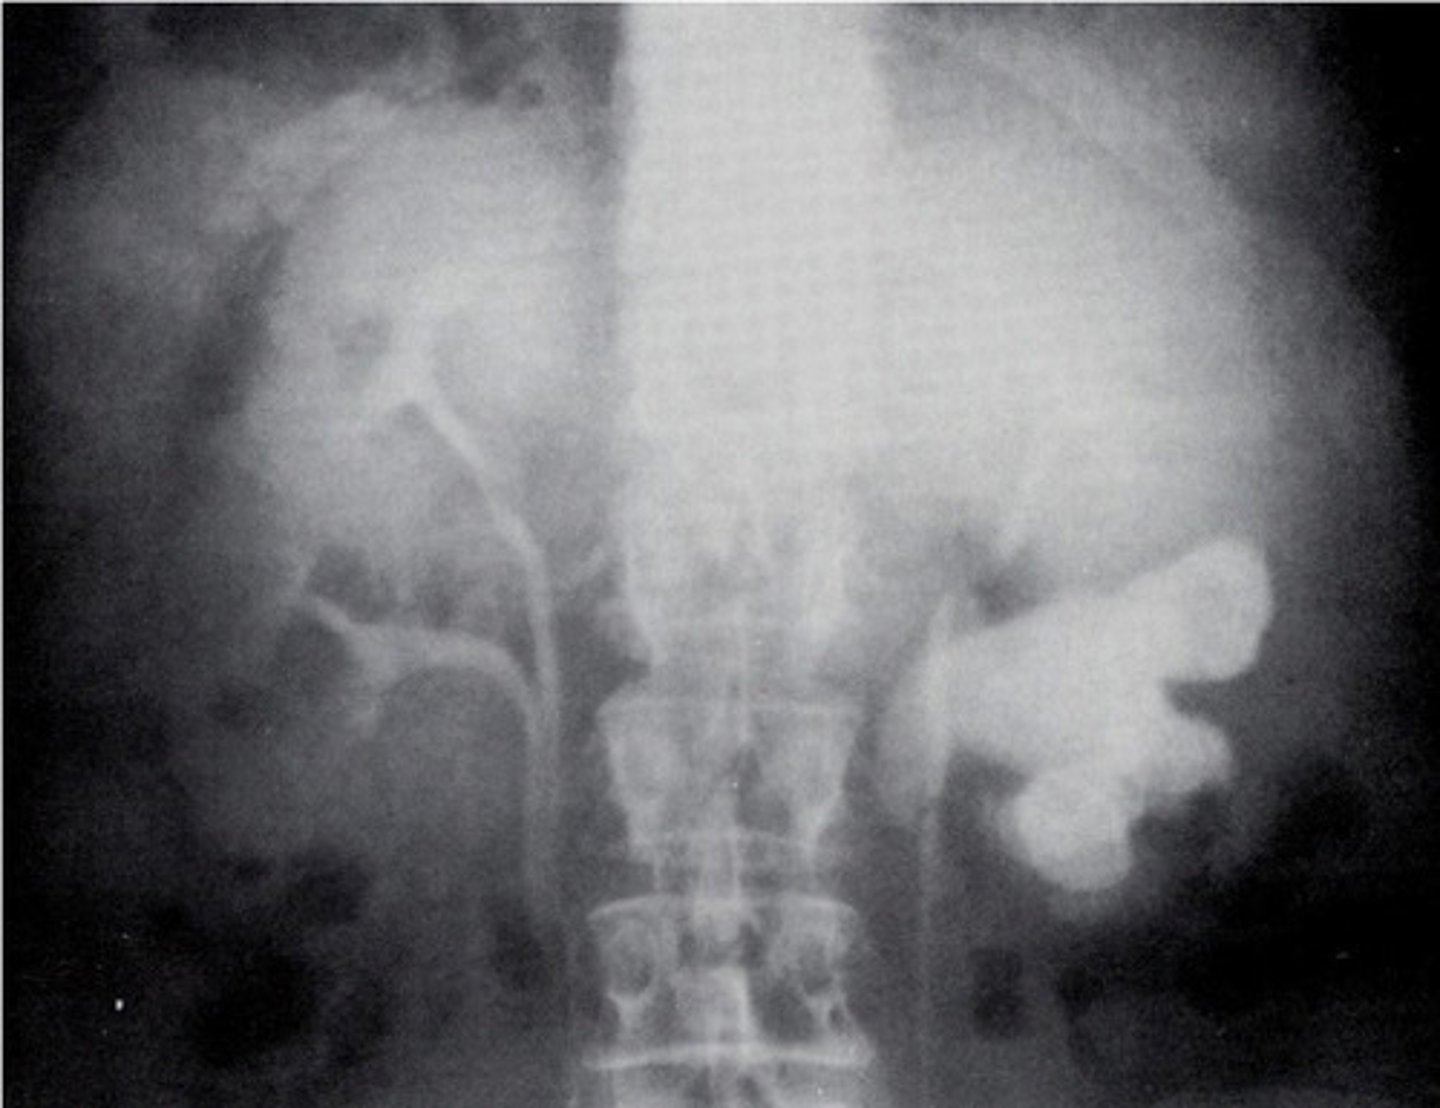

- Horseshoe Kidney

- Kidney stones

- What congenital anomaly occurs when the lower poles of the kidney fail to separate in the fetus and results in a horseshoe-shaped kidney?

- What can patients frequently develop because the ureters are displaced with this pathology?